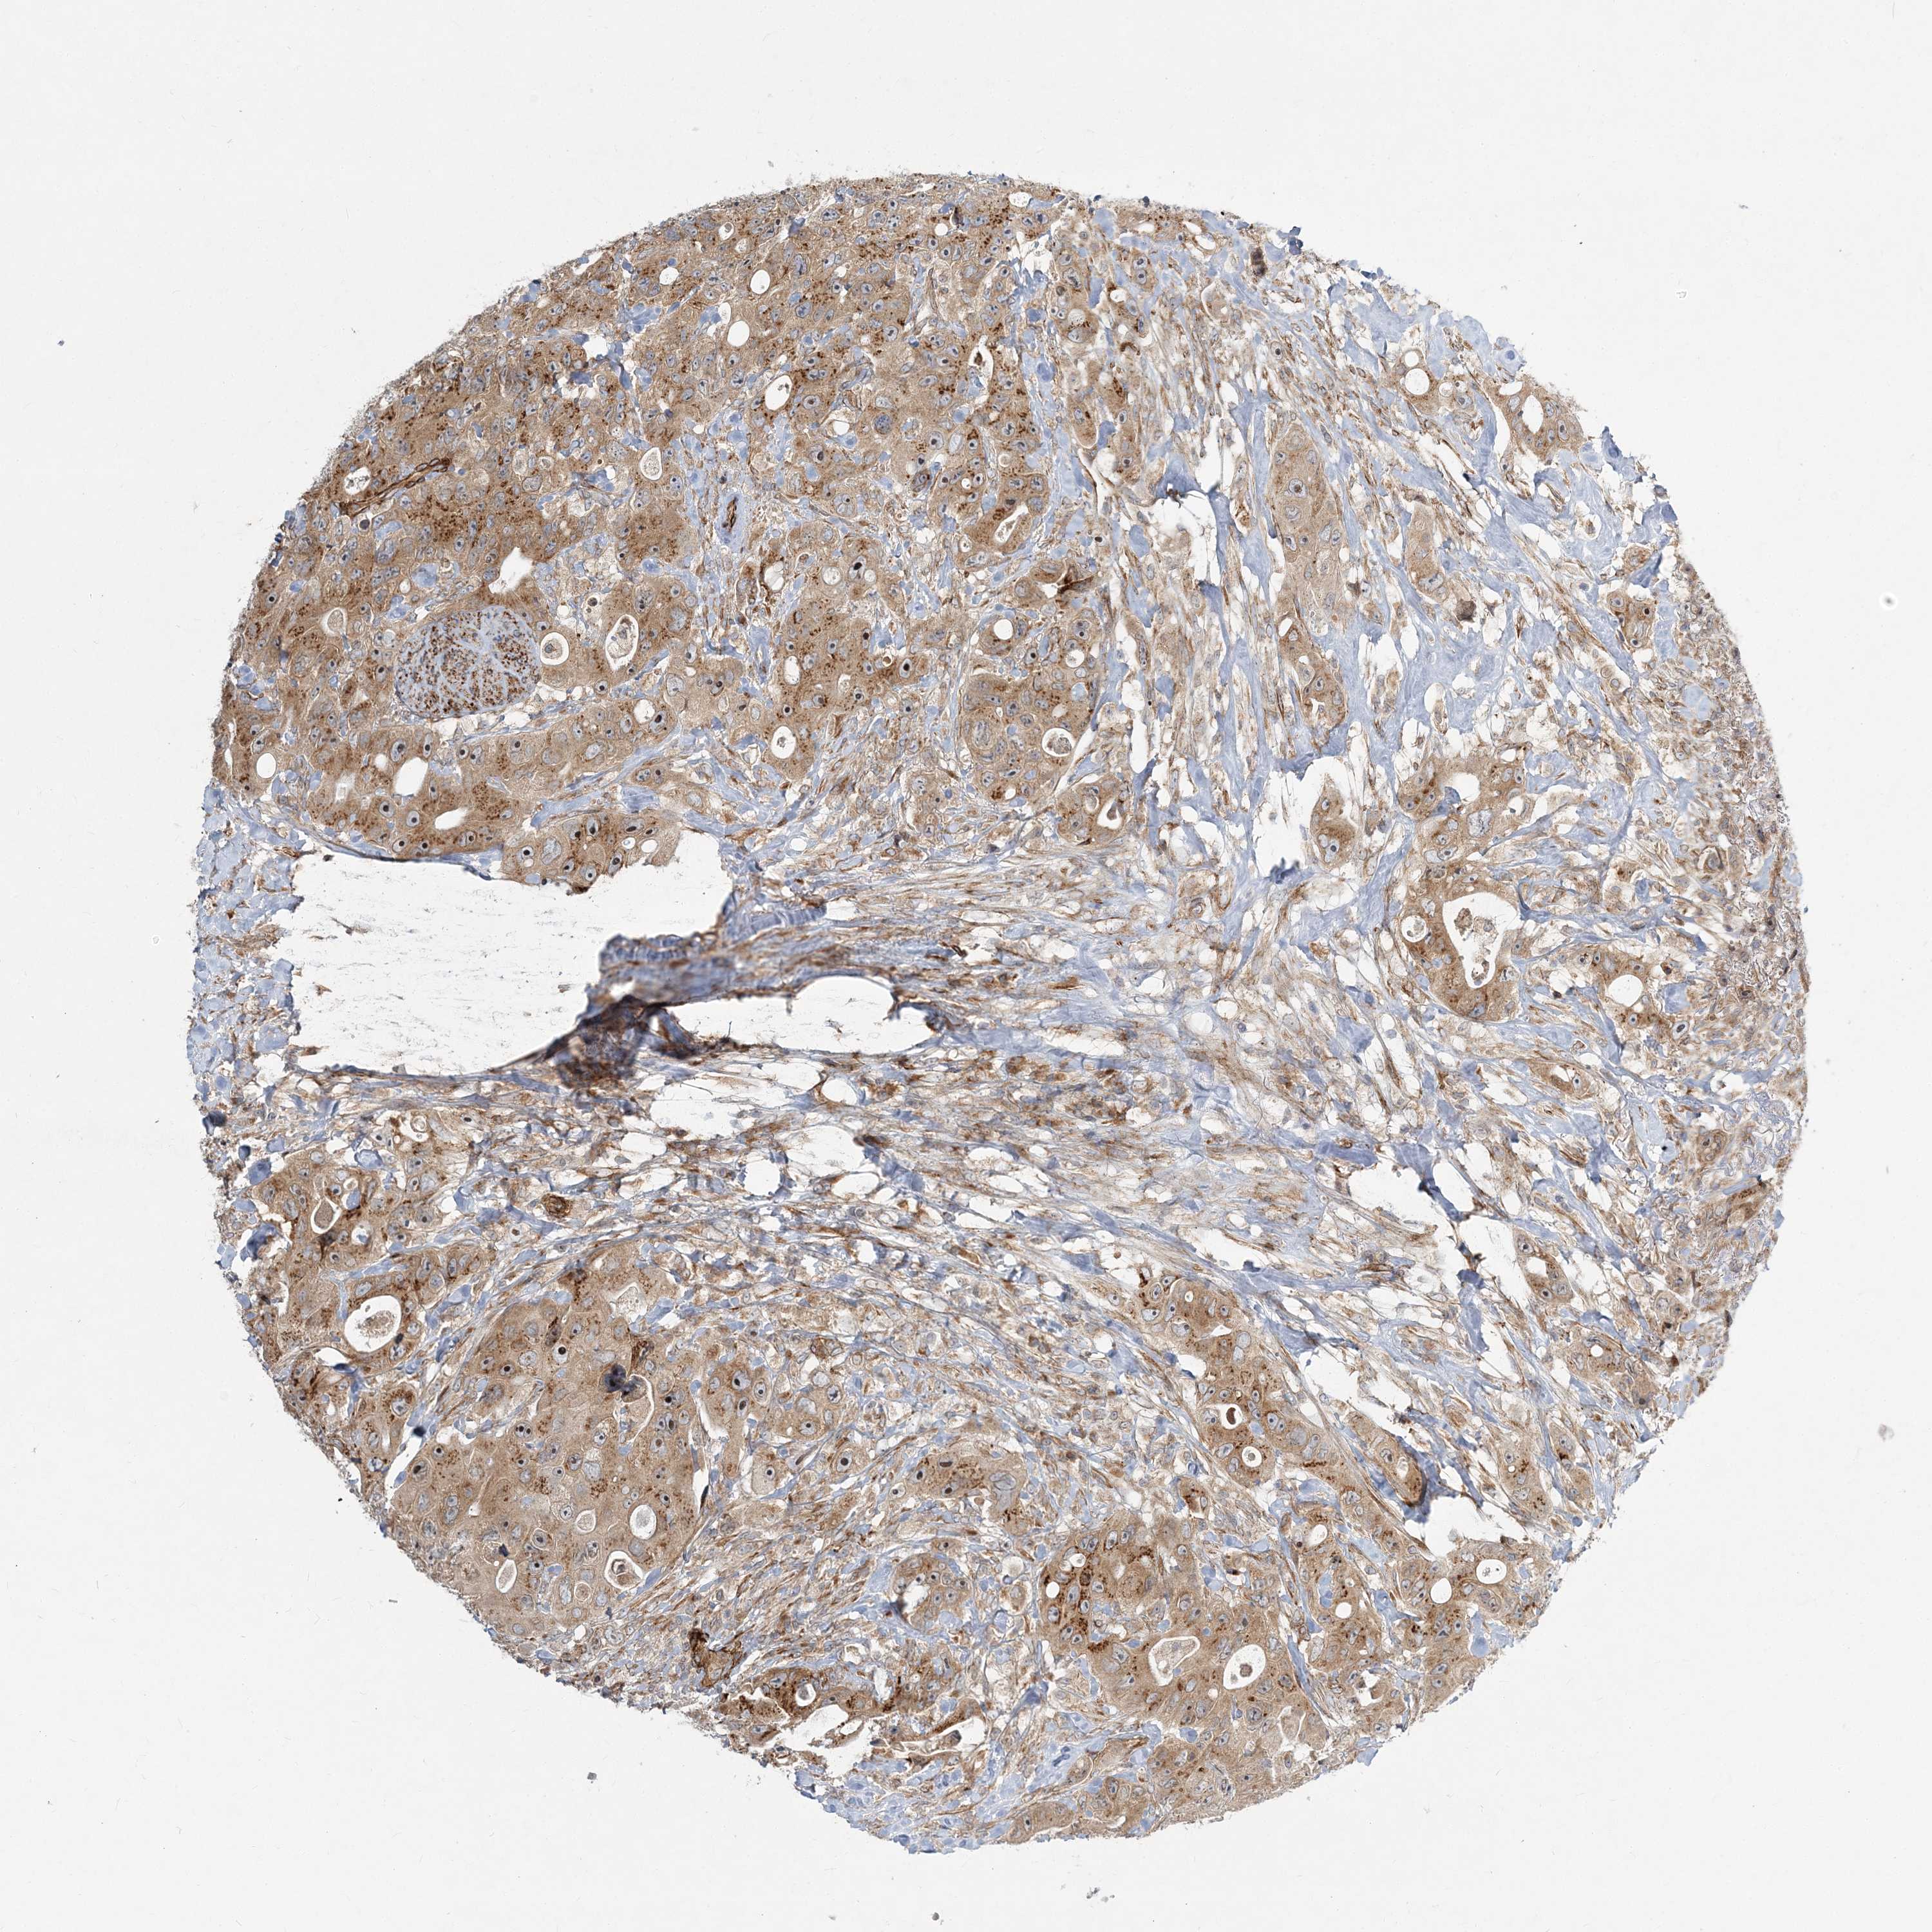

CANCER COLORECTAL CANCER Show tissue menu

Colorectal cancer

Human cancer

Colon adenocarcinoma

Rectum adenocarcinoma

COLON ADENOCARCINOMA (VALIDATION) - Interactive survival scatter ploti

NBAS is not prognostic in Colon Adenocarcinoma (validation)

Best expression cut offi

: 29.61

Median expressioni

: N/A

Median follow up timei

P scorei

N/A

5-year survival highi

For melanoma and glioma, 3-year survival is shown.

5-year survival lowi

TCGA RNA samplesi

RNA-seq data is reported as average FPKM (number Fragments Per Kilobase of exon per Million reads), generated by the The Cancer Genome Atlas (TCGA) .

Normal distribution across the dataset is visualized with box plots, shown as median and 25th and 75th percentiles. Points are displayed as outliers if they are above or below 1.5 times the interquartile range. FPKM values of the individual samples are presented next to the box plot.

Average pTPM 31.2

Number of samples 486